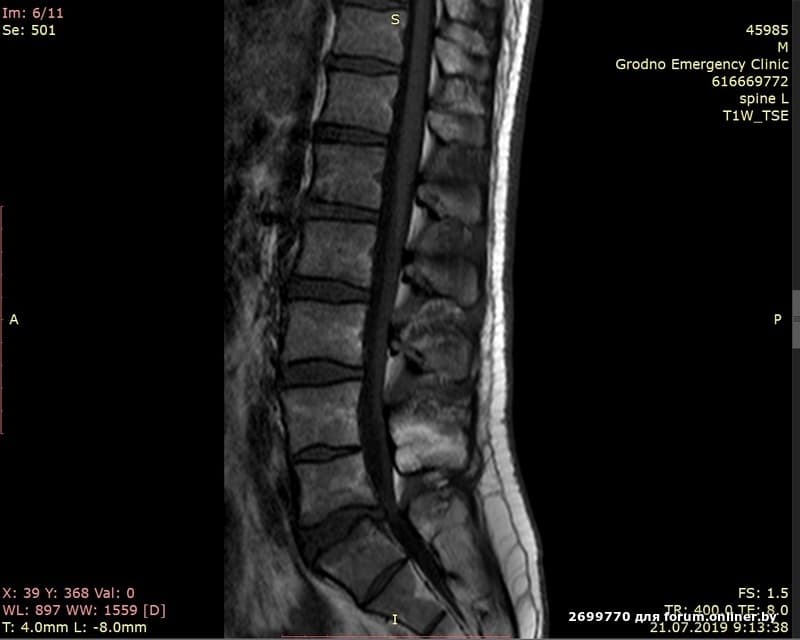

Здравствуйте! Может есть или была у кого похожая ситуация - что при таком заключении делать? Как облегчить страдания и надеяться на чудо. Правда ли что грыжа может сама обратно всасаться (ремиссия) или я не так понял. Кто -то говорит, что со временем сама отсыхает. Вообщем пока далёк от темы, хотелось бы услышать от братьев по несчастью бывалых т.с.

Сам был у нейрохирурга, тот сделал блокаду. Помогла. По остальному ничего толком так и не ответил. Только сказал, если онемевать промежность будет - на операцию в ту же секунду, на след. день буде уже поздно.